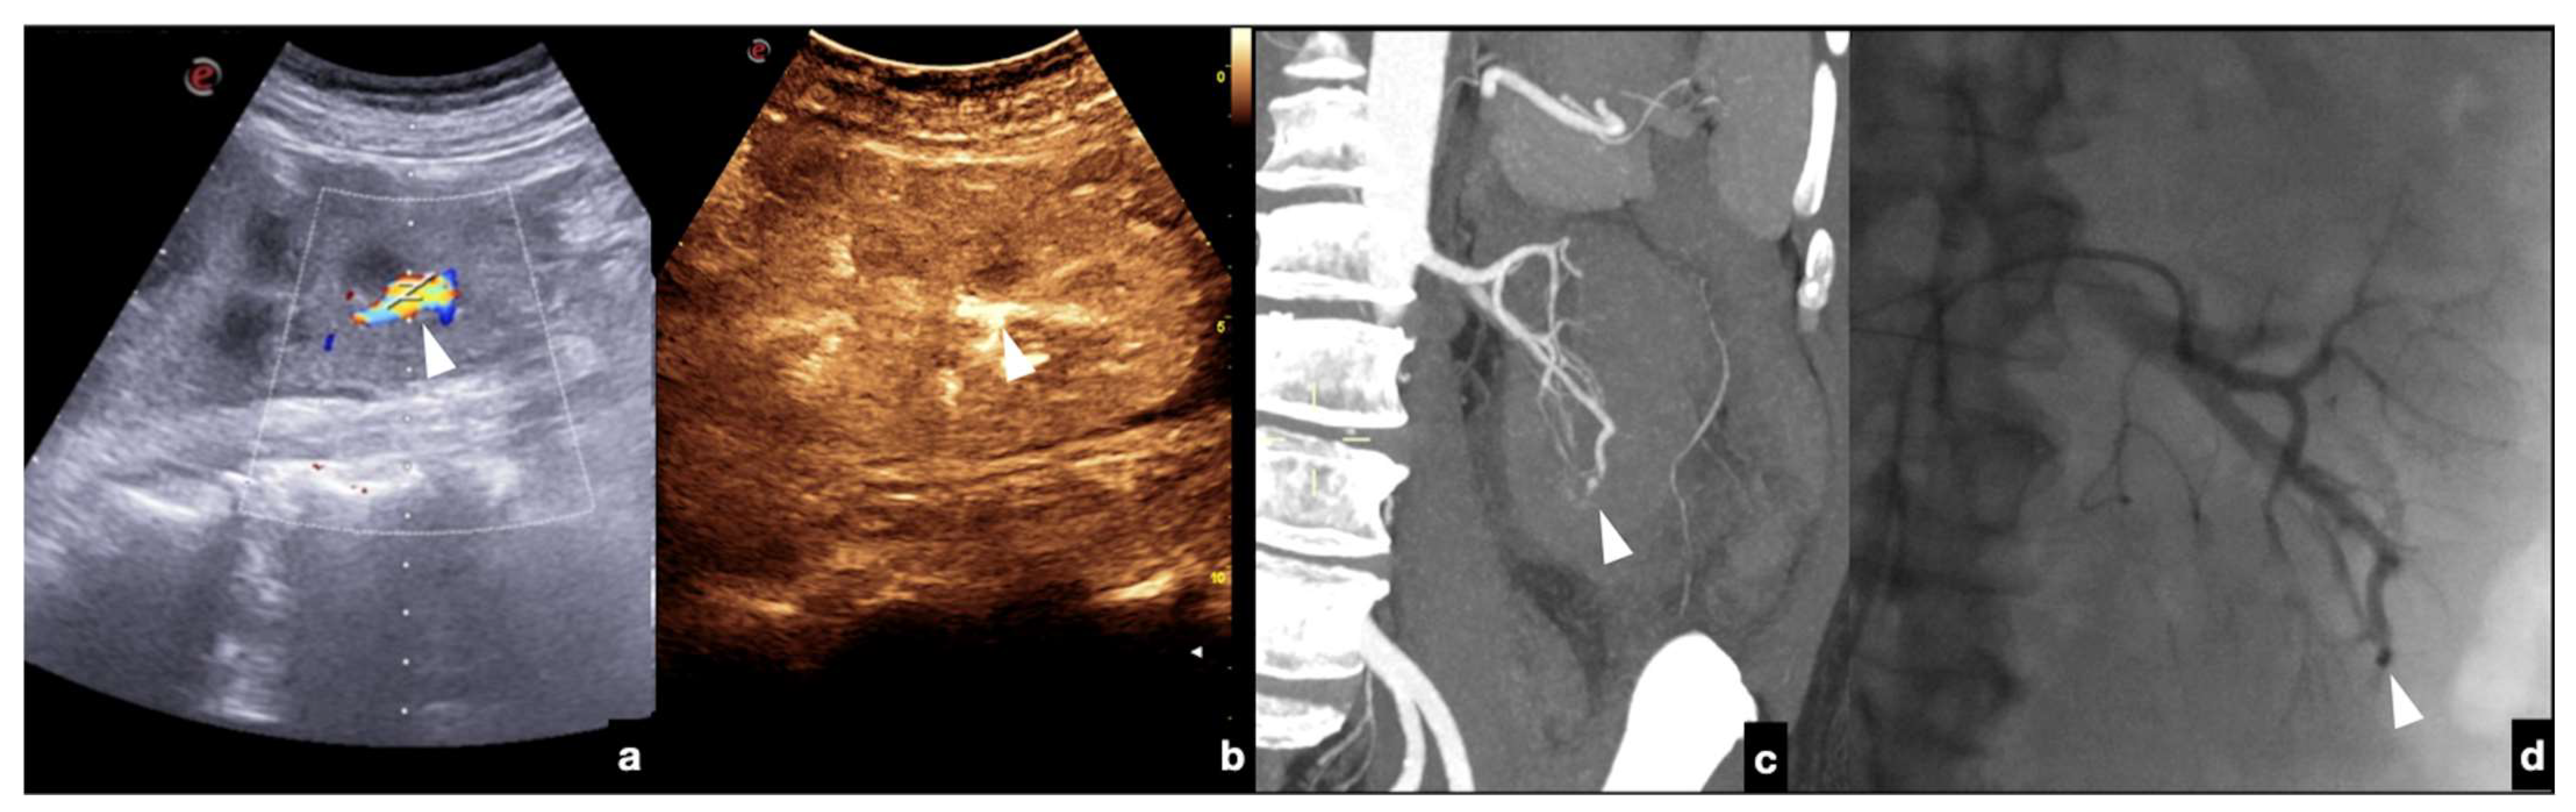

Arteriovenous fistulas consist of traumatic communication between the arterial and venous systems [1,30]. Fistulas are characterized as asymmetrical, early contrast opacification of a vein during the early arterial phase of the study (Figure 21).

Figure 21.

Companion case of Figure 2b. Renal arteriovenous fistula (white arrowhead) at color–Doppler US (a) and CEUS (b), confirmed (c) at contrast-enhanced CT scan (arterial phase, coronal MIP reconstruction) and subsequent angiography (d).